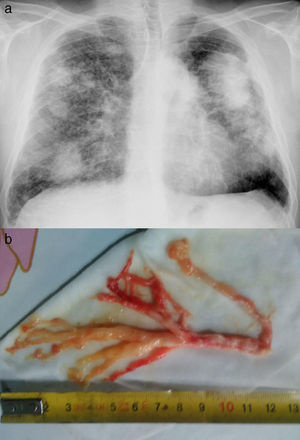

We report the case of a 49-year-old man with complicated silicosis and a history of pulmonary tuberculosis, non-smoker, with obstructive airflow limitation. He consulted due to episodes of intense dyspnea coinciding with expectoration of thick bloody secretions with a similar appearance to the bronchial tree (Fig. 1), occurring several days a week. The fiberoptic bronchoscopy showed no relevant findings and the pathology study of the bronchial cast revealed fibrinoinflammatory mucoid material, with abundant histiocytes.

Plastic bronchitis (PB) is a rare lung disease characterized by the formation and expectoration of bronchial casts that obstruct the bronchial lumen.1 It has been described as a complication of primary lymphatic abnormalities in patients with congenital heart disease (after the Fontan procedure), respiratory infections, cystic fibrosis, COPD, and allergic bronchopulmonary aspergillosis.1 We report a case of PB associated with silicosis. Treatment is controversial and therapeutic choices, which are based on isolated case reports, include mainly dornase alfa, low-dose macrolides, and nebulized hypertonic saline and acetylcysteine. Response to inhalation of fibrinolytics and nebulized heparin has been reported.1,2 In our patient, episodes of mucus plug expulsion reduced notably with the administration of prednisone (15mg/day) and nebulized heparin sodium (5000IU/12h).